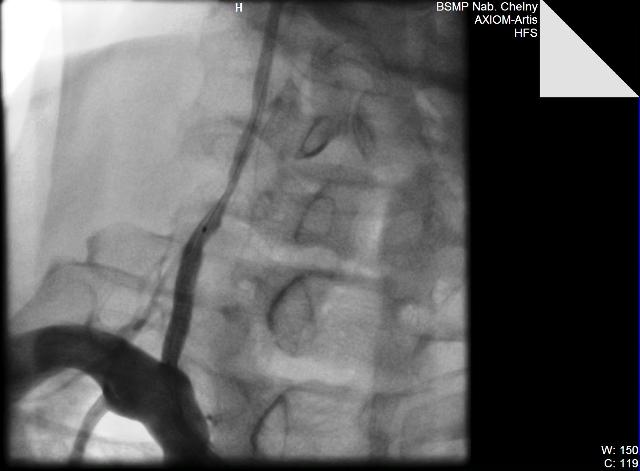

06.09.11. г. Выполнена ангиография ветвей дуги аорты, почечных артерий.

Диагноз: Генерализованный атеросклероз. Атеросклероз брахиоцефальных артерий. Стенозы внутренних сонных артерий слева 60%, справа - 50%, устья позвоночной артерии справа 70%. Сосудистая мозговая недостаточность II ст. Атеросклероз висцеральных ветвей аорты. Стеноз почечной артерии слева 70%. Синдром вазоренальной гипертензии. Синдром Лериша. Стенозы ОПА 85%, НПА 75% справа. Окклюзия НПА слева. Облитерирующий атеросклероз артерий нижних конечностей. Бедренноподколенное шунтирование справа в 1997 г.(шунт окклюзирован). Стеноз ОБА 60%, окклюзия ПБА, ПКА, берцовых артерий правой нижней конечности. Стенозы ОБА – 65%, ГБА 50%, ПКА 60%, окклюзия ПБА, берцовых артерий левой нижней конечности. ХАН нижних конечностей III степени.

06.09.11. БСМП г. Набережные Челны выполнено одномоментное стентирование устья правой позвоночной артерии, левой почечной артерии